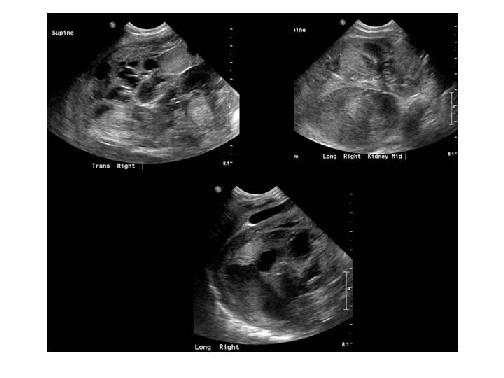

Bilateral multicystic dysplastic kidney disease

unilateral multicystic dysplastic kidney disease

unilateral multicystic dysplastic kidney disease

What is multicystic dysplastic kidneys?

disorder associated with unilateral cystic lesions

correspond to dilated collecting tubules

Enlarged

unilateral

nonfunctioning

What is the sonographic appearance of bilateral MDK?

multiple, round

various sizes

bladder not seen

olighydramnios

Poor Prognosis

What is the sonographic appearance of unilateral MDK?

multiple, round

various sizes

bladder seen

hydronephrosis